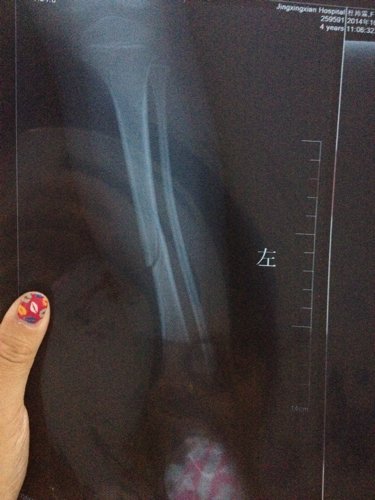

三周岁宝宝小腿胫骨青枝骨折,到医院医生没有复位直接打了石膏,但一个月去拆石膏拍片子还是有明显裂缝有影响吗?还有孩子什么时候可以下地负重,医生说拆石膏就可以下地,但是我看片子还是裂缝所以没敢让孩子走,正骨得人说得两个半月,现在看她得腿是没事动来动去挺自然。就是下地不敢使劲。请各位医生高手帮忙看看,下面的两张片子分别是刚碰着和一个月后得。非常感谢!!